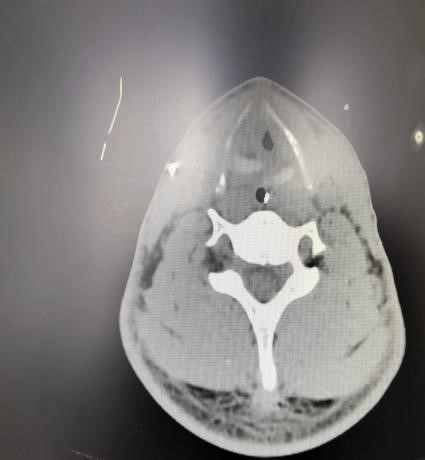

患者入院时虽神志尚清,但已出现声音嘶哑、颈部疼痛、胸闷气喘等危险信号,血氧饱和度持续下降。我院急诊团队评估后立即启动最高级别预警,迅速完成生命体征监护和检查的同时,敏锐地察觉到患者颈部正在快速肿胀,这是皮下气肿的典型表现,预示着气道可能存在严重破损。我院耳鼻喉科专家通过喉镜探查,做出了关键性判断:高度怀疑喉软骨骨折、气管断裂。后续CT检查结果印证了这一判断,患者双侧颌面部、颈部、胸部乃至纵隔内出现了大量积气。更危急的是,断裂处漏出的气体已形成双侧张力性气胸,双肺被压缩均近50%,心脏和大血管严重受压,情况十分危急!